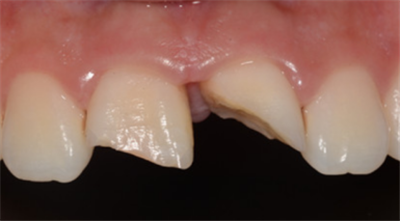

2.牙齿缺损:

楔状缺损

牙齿隐裂或折裂